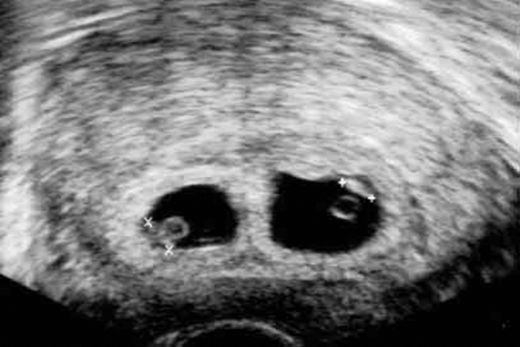

Gebelik süreci, birçok kadının yaşamında önemli bir dönüm noktasıdır. Bu süreçte meydana gelen fiziksel ve hormonal değişiklikler, bireylerin sağlık durumlarını etkileyebilir. İlişki sonrası kanama, gebelik döneminde sıkça karşılaşılan bir durumdur ve genellikle endişe kaynağı olabilir. Bu makalede, gebelikte ilişki sonrası kanamanın nedenleri, olası risk faktörleri ve dikkat edilmesi gereken noktalar ele alınacaktır. İlişki Sonrası Kanamanın Nedenleri Gebelikte ilişki sonrası kanama, farklı nedenlere bağlı olarak gelişebilir. Bu nedenler arasında şunlar yer alır:

Olası Risk Faktörleri Gebelikte ilişki sonrası kanama, bazı durumlarda daha ciddi sağlık sorunlarının bir göstergesi olabilir. Bu risk faktörleri arasında: